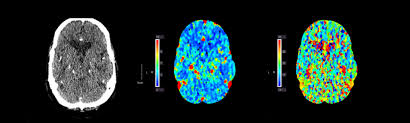

뇌출혈 초기증상.

나이가 들어감에 따라 뇌출혈, 뇌경색, 뇌졸중 등 뇌에 관련된 질병으로 현대인들은 몸살을 앓고 있는데, 오늘은 갑자기 나에게 다가올 뇌출혈 초기증상에 대해서 알아보고, 자가진단을 한번 하는 시간을 가져보는 것이 어떨까요?